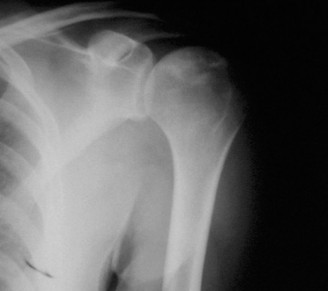

A 19-year-old, collegiate offensive lineman presents to your clinic with vague shoulder pain that has been on…